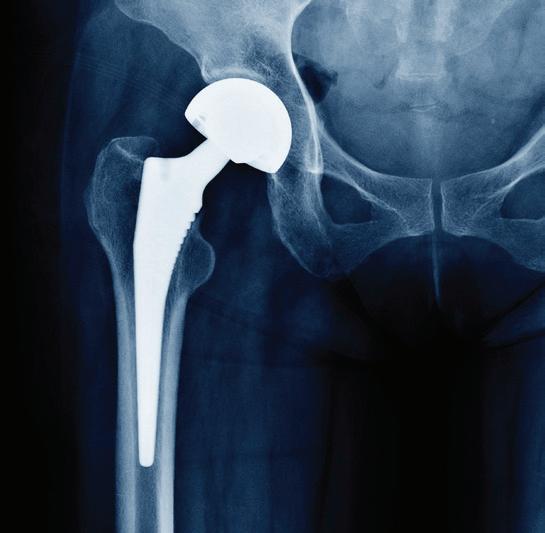

May 4 – Total Joint Replacement